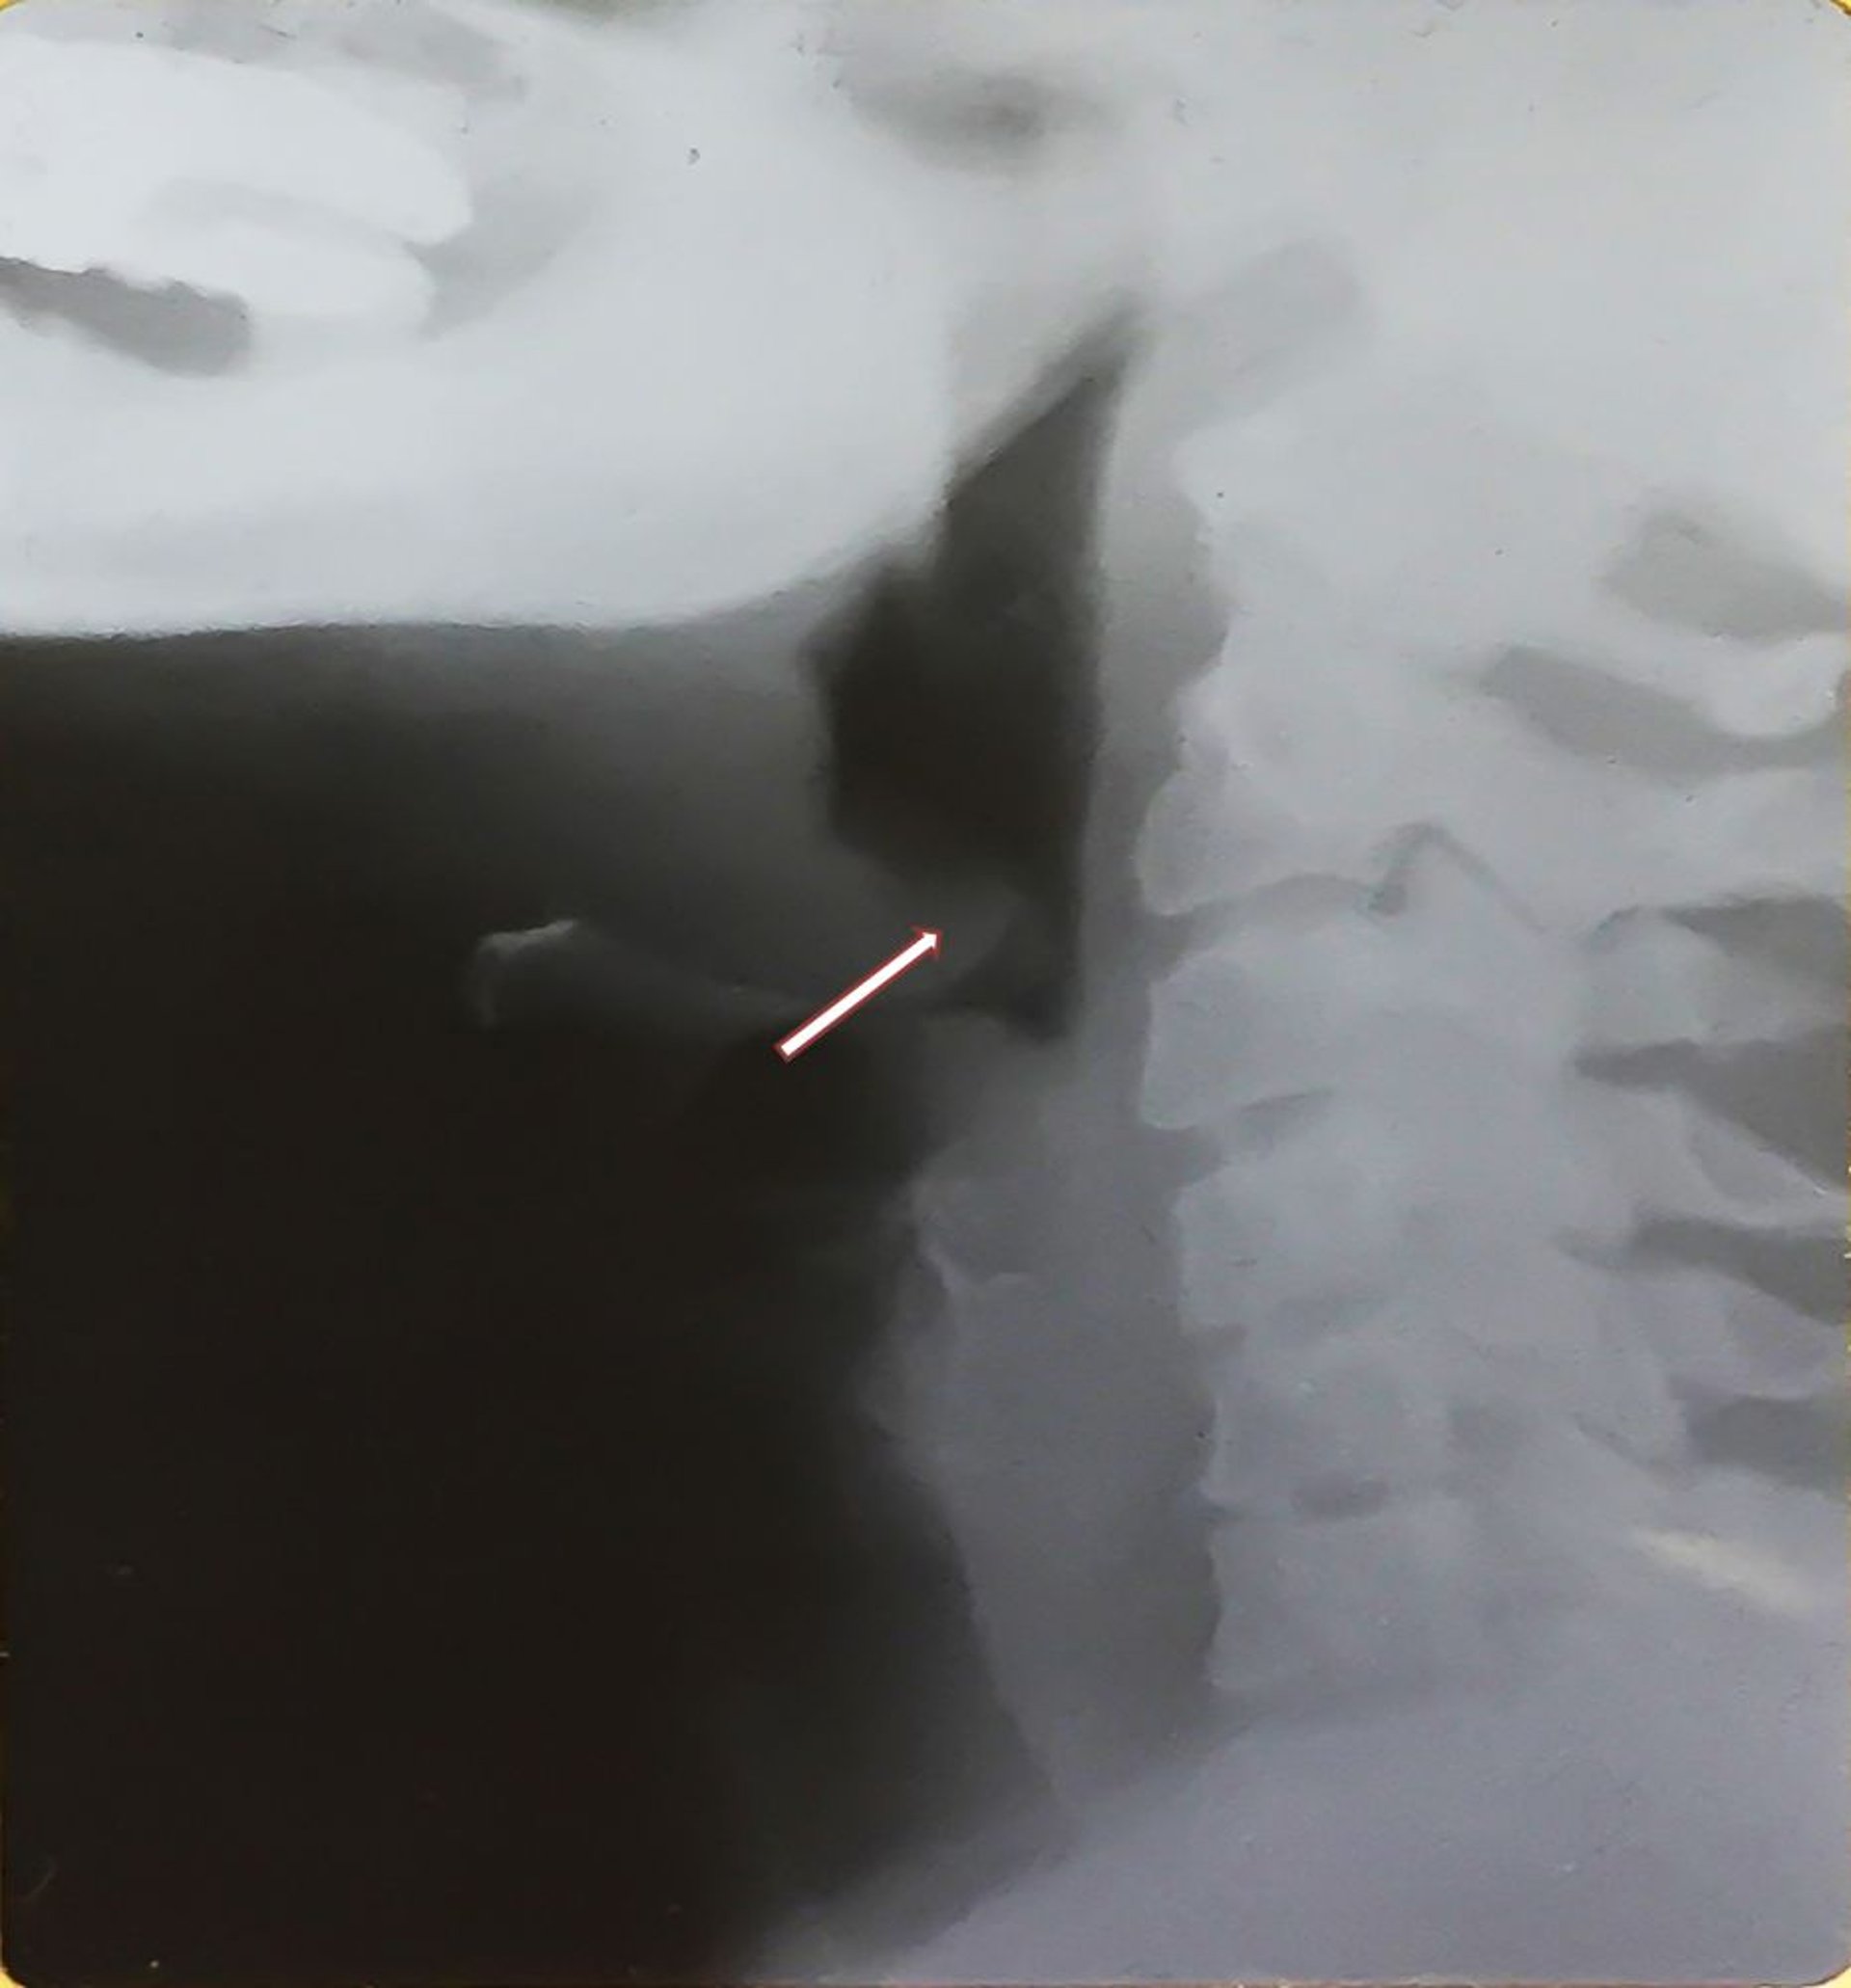

Эпиглоттит (у взрослых)

На этой рентгенограмме показаны увеличенный воспаленный надгортанник (симптом большого пальца - см. стрелку), характерный признак эпиглоттита, и отечная гортаноглотка. Обратите внимание на смещенный назад утолщенный надгортанник.